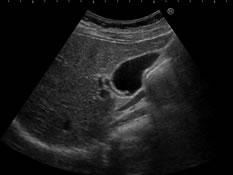

超音波検査

超音波検査は人の耳には聞こえない音(超音波)を利用した検査で、各臓器の状態、腫瘤の有無および性状を調べる検査です。

骨や空気は超音波を透さないため、骨の内部や骨のうしろにある臓器、空気を含んでいる肺や消化管は検査に不向きです。

放射線を利用した検査ではないので、被爆の心配はありません。

検査は少し暗い部屋で行います。肌に検査用ゼリーを塗布し、探触子をすべらせながら検査をすすめていきます。

腹部超音波検査

対象部位:肝臓・胆嚢・膵臓・腎臓・脾臓

目的:病気の診断や拡がり、良性・悪性の鑑別、転移の有無など。腹痛や発熱、肝機能障害の原因を調べるために実施されることもあります。

方法:検査の際には大きく息を吸ったり止めたりしていただき、この息止めの時に臓器を観察します。通常は仰向けで検査をしますが、観察する臓器によっては体の向きを変えていただくことがあります。

注意点:検査前4時間は禁食です。午前の予約であれば前日の食事は夜8時までに済ませ、検査当日は朝食を摂らずにお越しください。午後の予約であれば昼食を摂らずにお越しください。飲み物は水のみ摂取可能です。糖尿病の薬は服用しないでください。その他の薬はいつも通り水で服用していただいて構いません。

検査時間:約15分~30分。検査内容によって前後します。